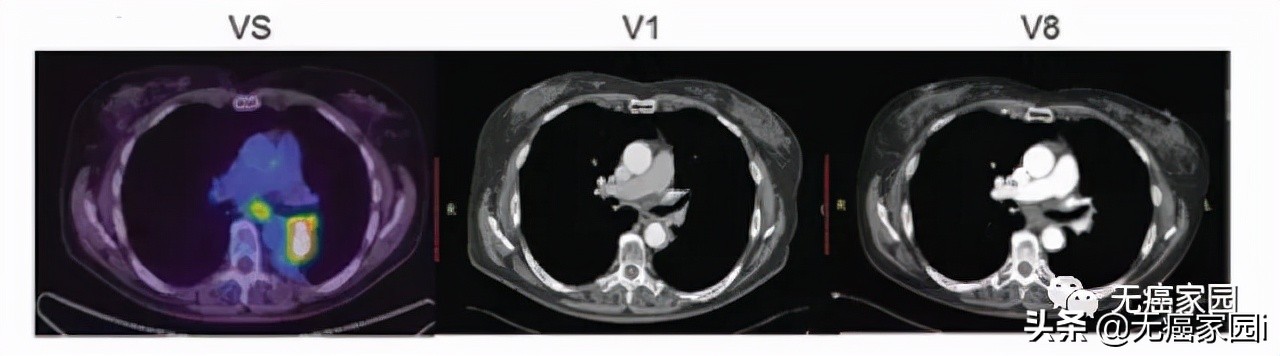

接下来,小编展示联合疗法中一个典型的成功案例,如图所示: 治疗1~2个月后复查,肺部肿瘤完全消失,并且疗效已经保持了18个月。

图为患者的治疗情况(图片来自NEJM)